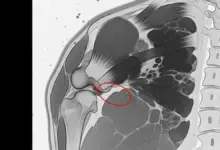

O exame avalia instabilidade, apreensão e padrão de dor, mas a confirmação costuma depender de ressonância magnética, muitas vezes com artrografia (contraste intra-articular), que melhora a visualização capsuloligamentar.